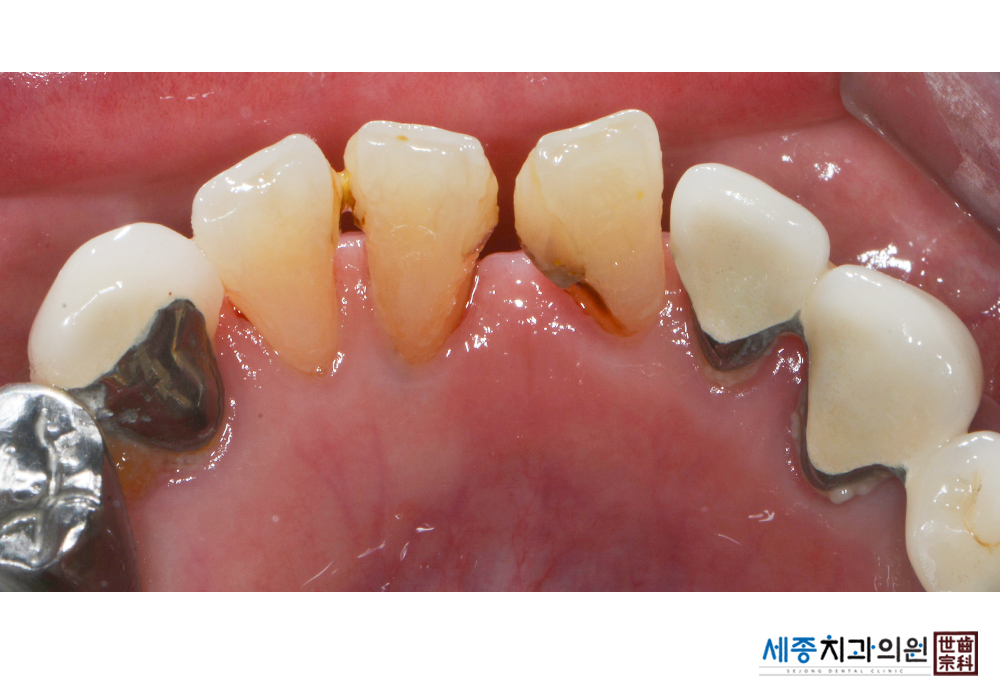

[스케일링] 치주질환 예방 스케일링 치료

치료전 : 2020-01-06

가글마취&저주파 스켈러를 사용한 스케일링